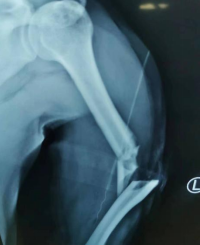

通过X光片检查显示李大哥左上臂为“肱骨开放性骨折、左尺桡骨骨折”,郑大伟主任迅速组织科室展开讨论,为其制定个性化手术方案。